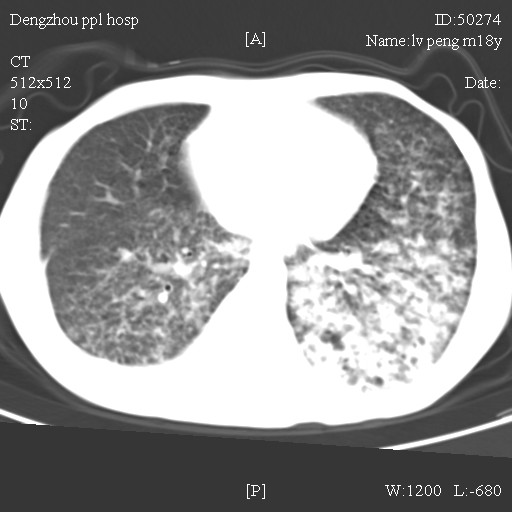

标题: CT10510:男.18岁,咳嗽咳痰两月.(有病理) [打印本页]

标题: CT10510:男.18岁,咳嗽咳痰两月.(有病理)

双肺布满大片状实变及网格状结节影,内参杂大小不等的气囊及空气支气管征,心脏增大。考虑:1 全身结缔组织疾病—系统性红斑狼仓?2 肺泡蛋白沉积症合并感染!

双肺布满大片状实变及网格状结节影,内参杂大小不等的气囊及空气支气管征,双侧胸膜腔少量积液,双下肺近膈面透亮度尚可,病人较年轻,病变较重(不知为什么上胃管?)考虑:1.胶原病肺部改变,2.组织细胞病x。结合实验室检查。

首先考虑组织细胞x病。两肺中上肺野多发囊腔,中下肺野内见多发小结节,并可见肺间质增厚。患者是男性,年龄较小。胶原性病变比较多见的类风湿、系统性红斑狼疮和硬皮病临床和影像均不是很支持,类风湿和系统性红斑狼疮的肺部表现最常见的是胸腔积液,硬皮病可见食管的扩张。

肺内多发斑片状、结节状、融合大片状及网格状影,多发薄壁空腔影,胸膜肥厚,纵隔、气管右移,考虑ⅲ型肺结核,多发空洞,继发肺间质纤维化。

双肺结核并播散.患者以肠梗阻入院,手术为肠结核.术后咳嗽做ct检查.